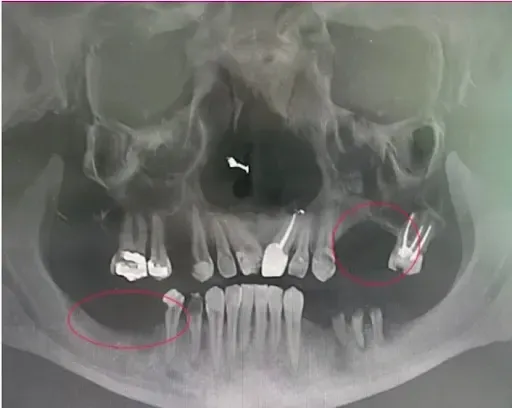

❌ Missing 1-2 teeth: Significant bone loss in 6-12 months

❌ Multiple missing teeth: Accelerated deterioration

❌ Infection present: Bone becomes "too soft to build on"

❌ Point of no return: Ineligible for implants permanently

✅ All infected teeth removed → eliminates source of infection

✅ Bone thoroughly cleaned → removes all infection

✅ Implants placed immediately → stimulates bone like natural roots

✅ Permanent teeth attached → full function restored